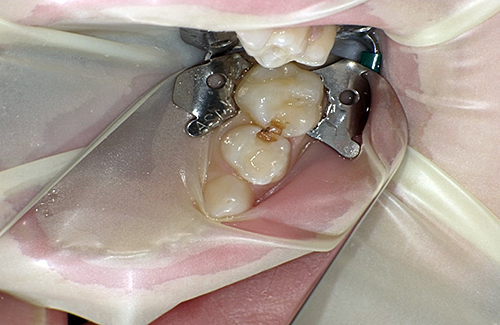

ラバーダム防湿

当院では、お子様のむし歯治療の際にラバーダム防湿というものを用いて治療を行っております。

一見、苦しそうに見えるかもしれませんが、実はこれを付けることによってラクに、

かつ安全に治療を行うことができます。

ラバーダム防湿のイイところ

①安全に治療が行える…低年齢の子は治療途中に突然動いたりすることがあって、歯を削るお道具で唇や舌を傷つける心配がない。

②お口の中に異物が入るのを防ぐ…削りカスや治療時に必要な薬品、冷却水がお口の中に溜まるのを防ぐ。

③早く治療を終わってあげられる…治したい歯だけをこのゴムのシートから出しているので早く治療ができる。

④正確な治療…詰め物が取れる大きな原因は唾液です。この装置は唾液からの感染を防ぐので正確な治療ができます。

※もちろん、風邪などの鼻づまりで鼻呼吸ができず口呼吸でも苦しそうな場合、予約を取り直してもらうか、ラバーを使用しない簡単な治療からするようにします。

やむを得ず治療をする場合は、ラバーを持ち上げて口呼吸ができるようにしながら、苦しくないか注意を払いながら治療を行います。

また、ゴムアレルギーのお子様にはラテックスフリーのラバーダムも用意しています。

どこにむし歯があったかな?

むし歯はないように

見えるけど

削ってみると…